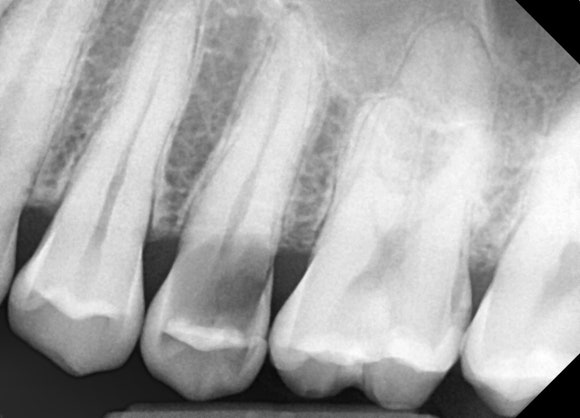

20250411

치아 머리 부분이 까맣게 보입니다.

충치 때문에 치아가 녹아서

텅 비어있기 때문입니다.